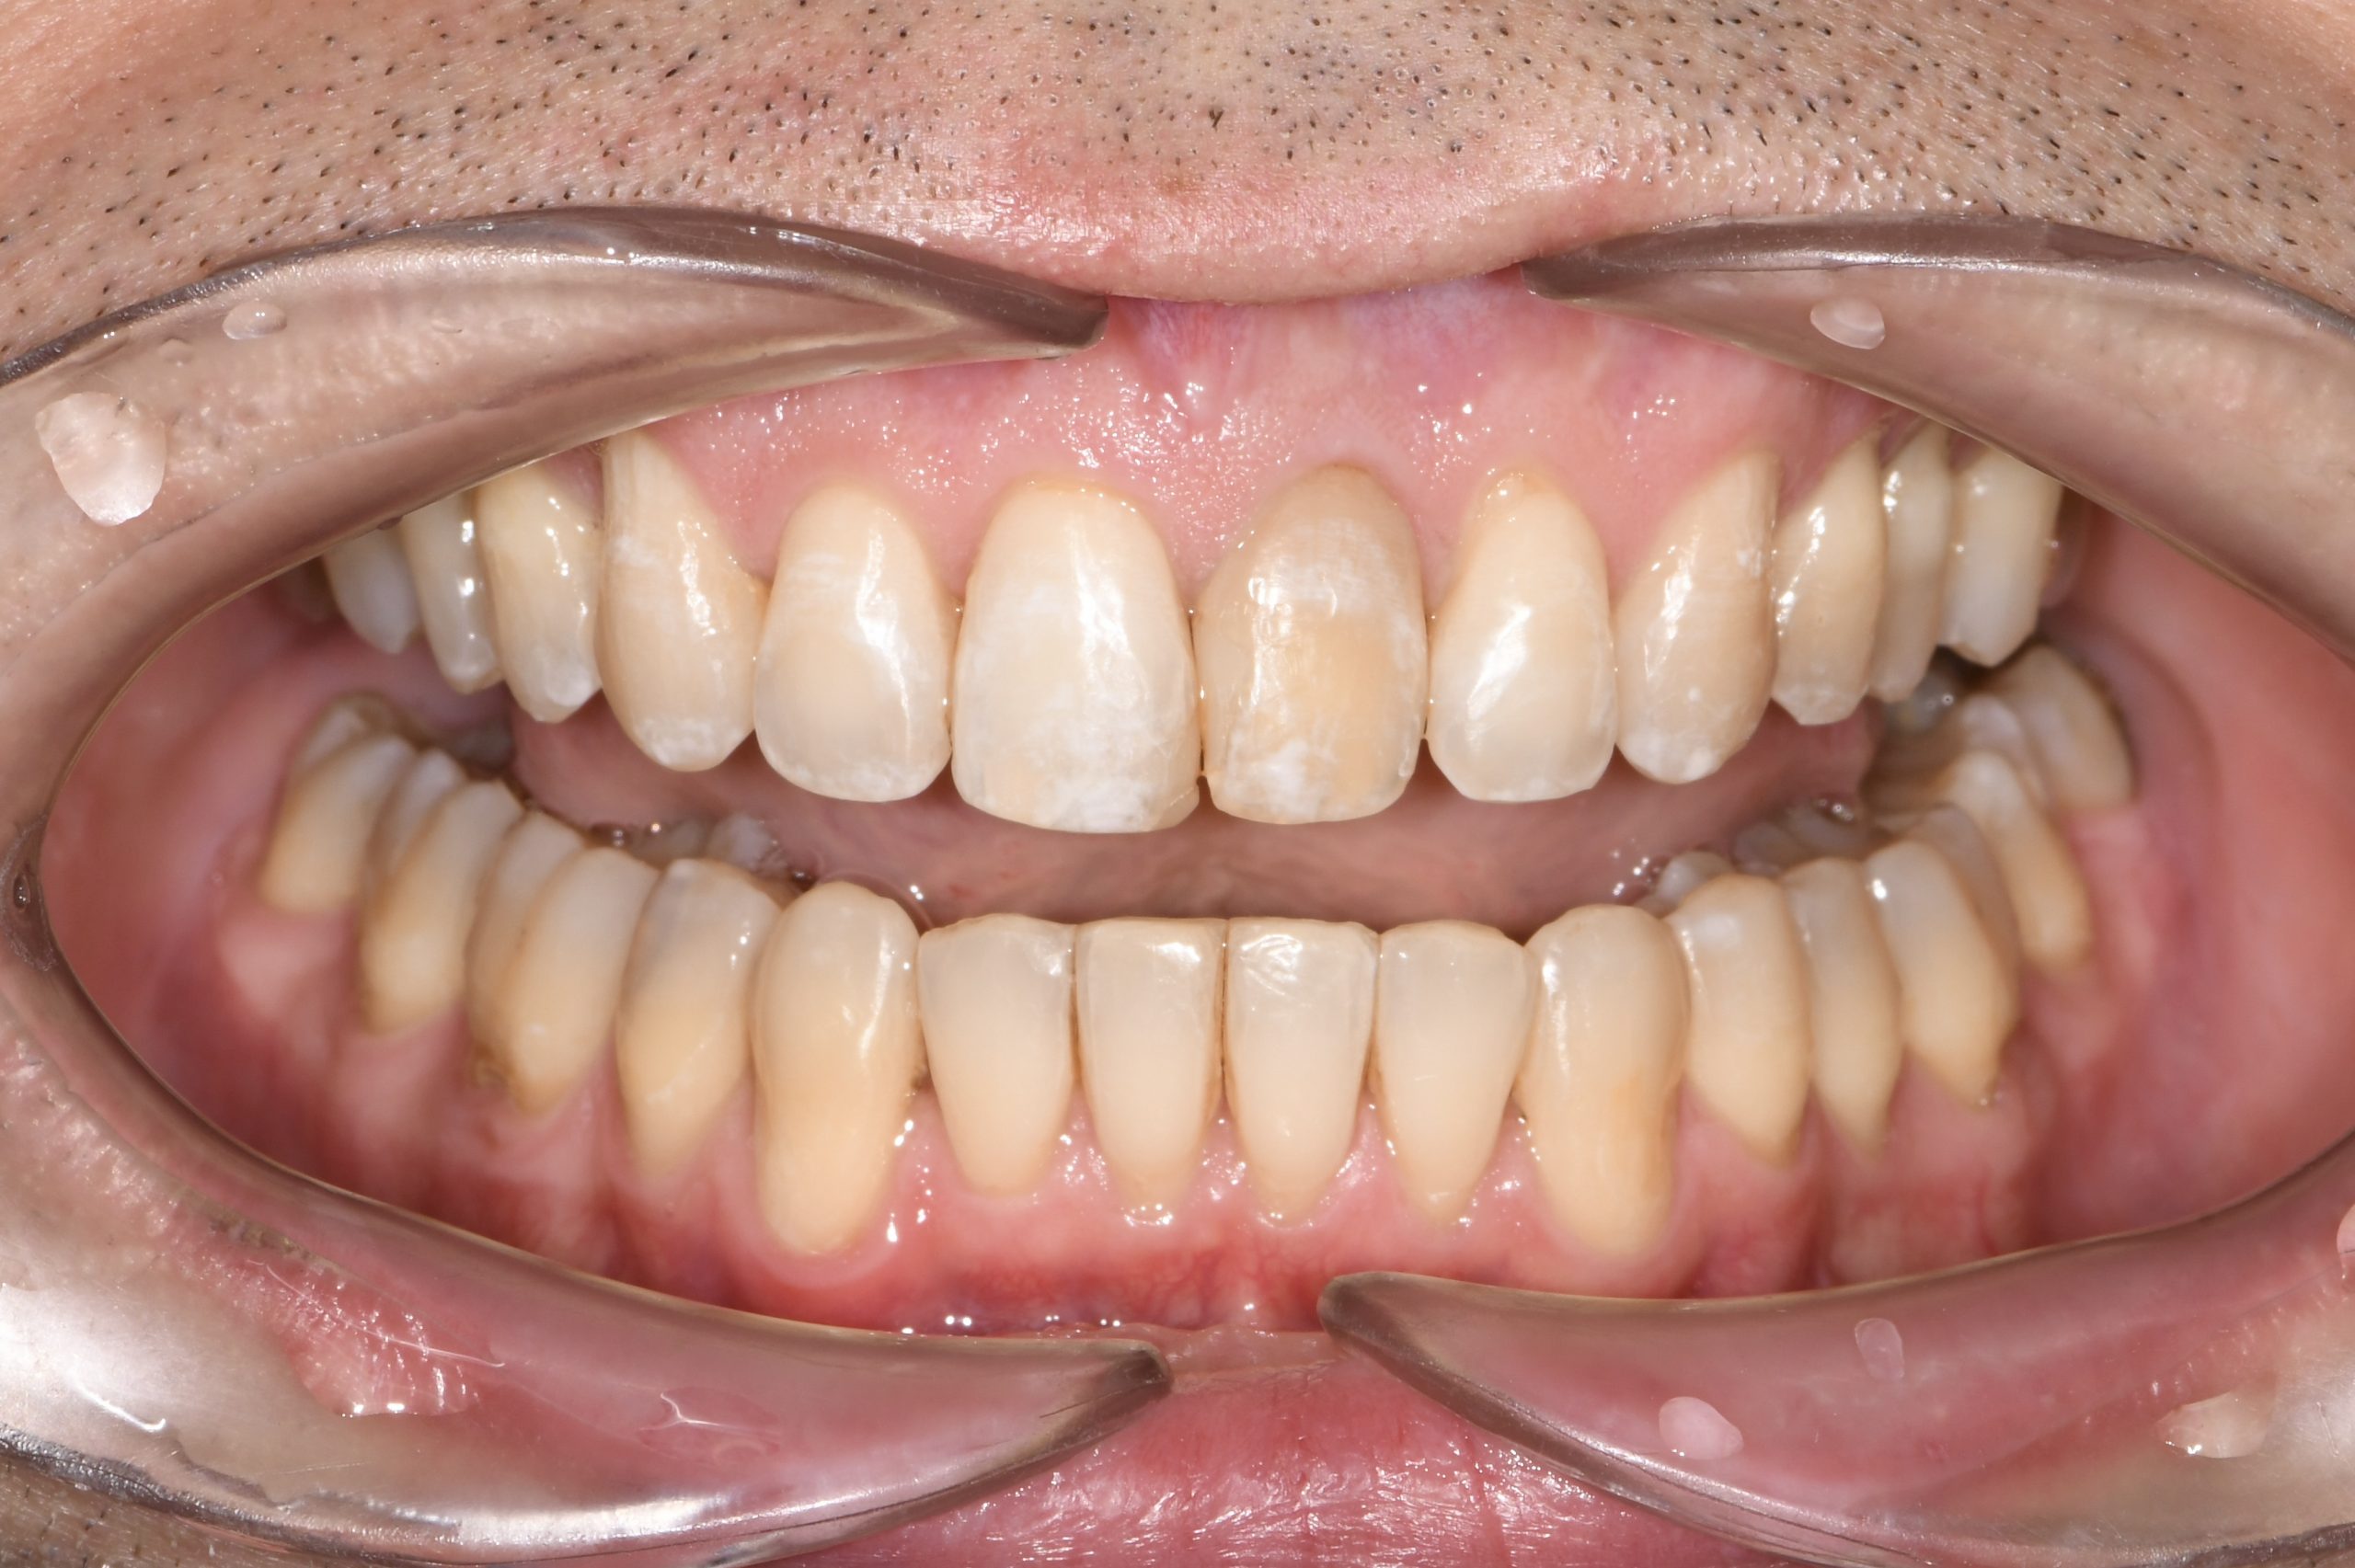

Az elmúlt évekből rengeteg szakmai referenciát tudnánk bemutatni, amelyek különböző fogszabályozási problémákat oldottak meg. Válogatva a több száz esetből, ezen az oldalon olyan képeket, információkat igyekeztünk bemutatni, amelyeknek a segítségével a jövőbeni pácienseinknek azt tudjuk üzenni: A Te fogsorod is lehet gyönyörű!

(Képeket a Pácienseink külön írásos beleegyezésével mutatjuk be!)